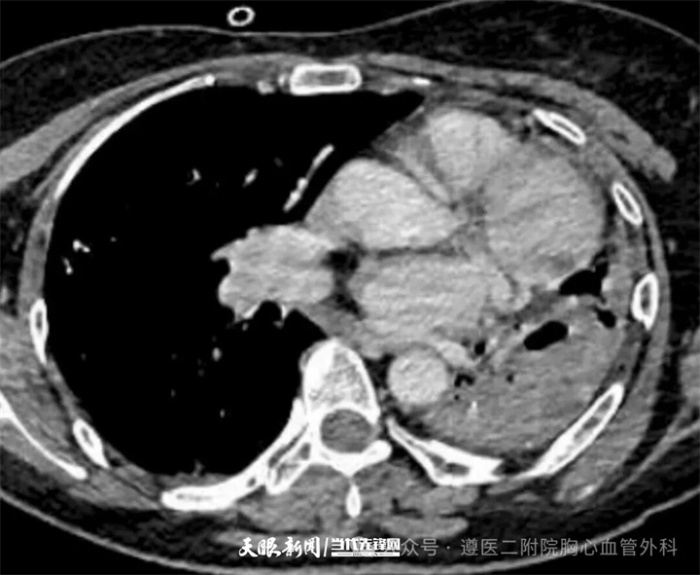

近日,遵义医科大学第二附属医院胸心血管外科成功救治了一名因“左侧结核性毁损肺”发生大咯血的危重患者。该患者自生病40年来反复发生咯血,本次发病咯血量大,检查提示左肺毁损已无功能,切除病肺止血救命刻不容缓。遵医二附院胸心血管外科团队在与死神的竞速中争分夺秒,顺利完成左侧胸膜腔粘连松解及全肺切除术,让患者转危为安,用精湛医术为患者筑起生命防线。

入院后,胸心血管外科团队迅速评估病情,结合患者病史与影像学检查,明确诊断为“左侧结核性毁损肺”。由于患者左肺已完全毁损且反复大咯血,保守及介入治疗均宣告失败,急诊手术成为唯一的救命选择。